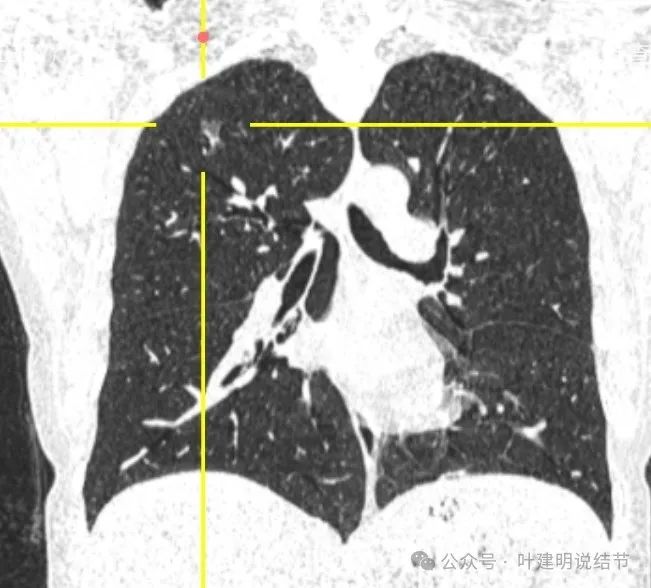

2024年9月病灶仍在,实性成分较前略显明显,矢状位清楚显示穿行血管壁毛糙。冠状位显示分叶以及病灶与血管间没有间隙。